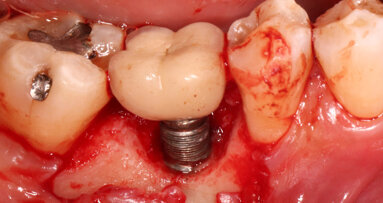

KHARTOUM, Sudan/LAS VEGAS, US: Accurate impression is crucial to the long-term success of dental implants since inaccuracies or errors occurring at any stage of the superstructure construction may result in complications or implant failure. A recent study evaluated the accuracy of the open and closed implant impression techniques in partially edentulous patients and found no significant differences between these two methods.

Researchers from the Department of Oral Rehabilitation in the Faculty of Dentistry at the University of Khartoum and the School of Dental Medicine at the University of Nevada, Las Vegas took 80 impressions from 40 patients—two for each patient—using the open-tray technique for the first one and the closed-tray technique for the second. Eighteen impressions in the maxillary arch and 22 in the mandibular arch were made. Of these, 13 were positioned in the anterior region and 27 in the posterior region. The horizontal distances between two impression copings were measured and compared to similar measurements on the master casts. In addition, the presence or absence of marginal discrepancies was evaluated.

The research team did not find any significant differences regarding horizontal measurements or in the marginal relationship for the two impression techniques, except for differences between the anterior and posterior regions for the closed-tray technique. There were also no statistically significant differences in the impression accuracy between the maxillary and the mandibular arches. In addition, there were no statistical differences between the two techniques for the intra-oral horizontal distances, compared with similar horizontal measurements on master casts.

“Within the limitation of this study, there were no differences in the impression accuracy between the open- and closed-tray techniques, in partially edentulous jaws with two adjacent implants. Also, there were no differences between the two impression techniques regarding marginal discrepancy. The position of the implant, in the maxilla or mandible, had no effect on the impression accuracy of both techniques,” the study authors concluded.